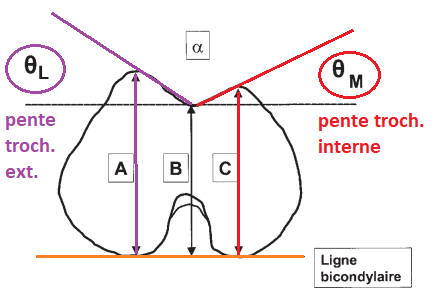

Pente trochléenne

Bascule rotulienne

Grand axe de la rotule (G) et Condyles (C)